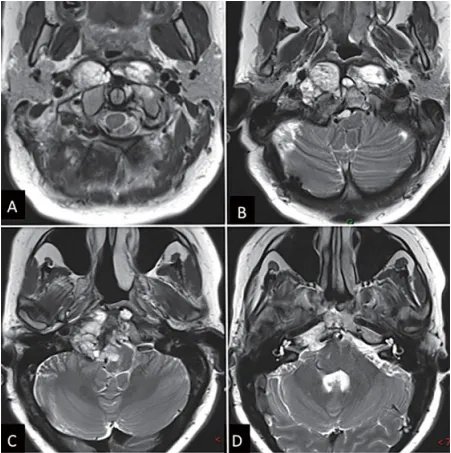

Carol查找、阅读了大量资料,发现福教授在颅颈交界区的手术治疗上有着大量成功的手术案例,因此寻求他的手术。MRI显示,肿瘤位于下斜坡,并向周边广泛延伸,右侧C1和C2、岩尖水平均见有肿瘤,右侧椎动脉被肿瘤包绕,脑干受压迫(▼图1)。CT扫描也显示骨质广泛的肿瘤浸润。

图1:内镜下鼻内镜入路前的术前影像。(A-D)MRI T2 WI显示一个较大脊索瘤延伸至椎前间隙和齿状突周围。肿瘤横向延伸至舌下管和颈静脉孔,并向内侧延伸至硬膜内间隙。肿瘤从斜坡中部延伸至枢椎齿状突周围。